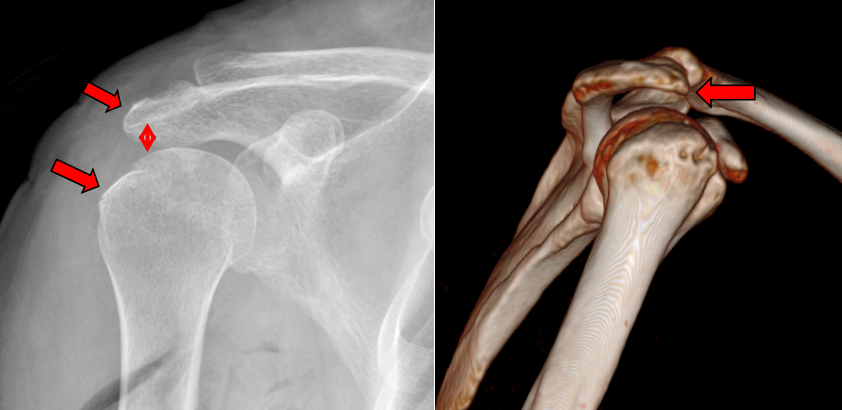

王某某,女,61岁,3个月前因摔伤致右肩部肿痛伴功能受限,于当地医院住院1周后因右肩部疼痛加重伴活动受限来我院就诊。行右肩MRI检查示:右肱骨大结节骨折,伴冈上肌腱部分撕裂、肩胛下肌腱损伤、肱二头长头肌腱炎、关节囊粘连。

4. 关节镜下关节囊松解、肩峰成形、单排铆钉改良Mason-Allen缝合。